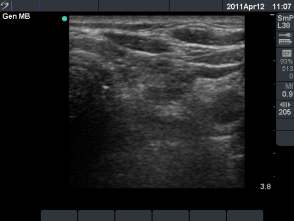

6 weeks after the last session (fourth row of images):

Clinical presentation: the patient had no complaints.

Palpation: no abnormality.

Serum parathormon-level 32 ng/dL (normal values: 10-65).

Ultrasonography: the cysts almost disappeared.